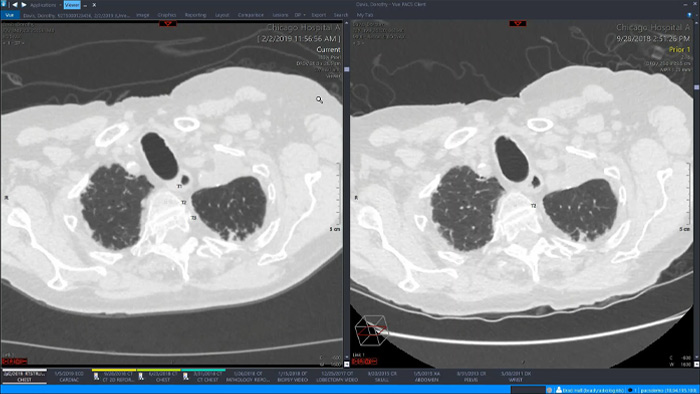

Let’s take a look at some of the immediate benefits of a unified approach. A single, unified workspace for radiology would incorporate advanced 3D post-processing and image distribution capabilities, opened in an additional viewer tab for ease.

A unified workspace would mean that users can easily launch the relevant analysis tools from among the 70+ advanced applications available across multiple clinical domains. Artificial Intelligence can play a role by automating tasks and workflows, predicting usage patterns.

An all-in-one workspace, fully integrated with the enterprise imaging platform and embedded in the diagnostic viewer, offers simple, efficient access to all needed tools across clinical domains. One-click access to advanced visualization tools – such as virtual colonoscopy, 3D processing, and spectral imaging – allows for efficient interpretation and supports diagnostic confidence.